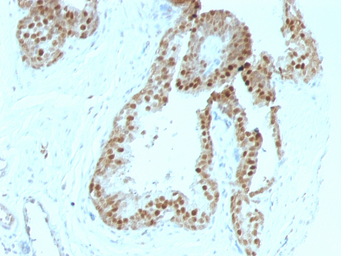

IHC-P analysis of human prostate carcinoma tissue using GTX34941 p57 Kip2 antibody [KIP2/880].

IHC-P analysis of human colon carcinoma tissue using GTX34941 p57 Kip2 antibody [KIP2/880].